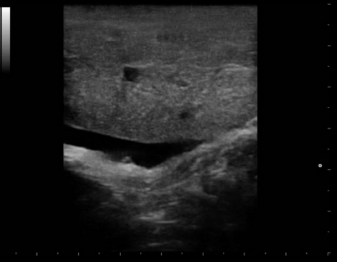

Eight intact female cats were referred for the treatment of FAC between 2015 and 2020. Ages at admission ranged from 8 to 12 months (Table 1). Four cats were domestic shorthair (C1, C2, C5, and C8), two cats were Maine Coon (C3 and C6), and two were Persian (C4 and C7). None of the cats received exogenous progestins but had a history of recent heats. Four cats (C5, C6, C7, and C8) had been mated and were between the 25th and 32nd day of pregnancy at presentation. The mammary glands were bilaterally enlarged, and no milk secretion was detected. Skin ulceration, inflamed, and painful mammary glands were present in six cases (C1, C2, C3, C5, C7, and C8) (Fig. 1a and b). General signs (tachycardia, lethargy, and anorexia) were strongly related to these changes. The diagnosis of FAC was based on clinical symptoms. Fine-needle aspiration biopsy of the mammary tissue was performed to support the clinical diagnosis. The combination of glandular-epithelial tissue and mesenchymal cells and the absence of prevalent immune cell populations in the cytologic smears allowed to exclude malignant growth or mastitis. Ultrasound examination of the mammary gland and doppler was employed to evaluate the structure and vascularization of the enlarged gland. FAC presented mainly as a well-circumscribed solid mass of granular, slightly hyperechoic texture, with regularly delimited margins. There was a uniform distribution of vascularity. Anechoic areas were present in the parenchyma and outside the margins (Fig. 2). Owners gave their consent to conservative treatment to preserve fertility and the integrity of the mammary glands. Mastectomy was not performed in any cases. Non-pregnant cats (C1, C2, C3, and C4) were treated on two consecutive days with subcutaneous injections of 15 mg/kg Aglepristone (ALIZIN; Virbac, Carros, France). The treatment was continued weekly with a single injection until the resolution of signs. If signs of ulcers, inflammation, or necrosis were evident in at least one mammary gland, 12.5 mg/kg q 12 hours of amoxicillin / clavulanic acid tablet formulation (SYNULOX; Zoetis, Rome, Italy) and 0.1 mg/kg q 24 hours of meloxicam (MELOXORAL oral suspension 0,5/ml; Dechra Veterinary Products, Turin, Italy) for the first day, followed to 0.05 mg/kg q 24 hours was given for 5–6 days. Furthermore, an oral dietary supplement containing maltodextrin and bromelain (BROSPET; Aurora biofarma, Milan, Italy) was administered once a day for the treatment period. Ulcers were treated topically twice daily with a cream containing hypericum and neem extract (HYPERMIX; Rimos, Mirandola, MO, Italy). The enlarged mammary glands were daily massaged with an emollient gel based on Aloe vera (ALOPET GEL; linea Angel Ariel, Grancona, VI, Italy). Two of the four pregnant female cats were treated with the same schedule for the severe enlargement and ulceration of the mammary glands (C5) and early signs of fetal resorption, deduced by the slow heart rate and the increased echodensity of amniotic fluid (C6). After 1 week, they presented bloody vaginal discharge, and ultrasound revealed four placental remnants in a cat (C6) (Fig. 3). Cloprostenol (ESTRUMATE; MSD Animal Health, Segrate, MI, Italy) at the dosage of 1.5 mcg/kg was given for three consecutive days to facilitate uterine emptying. Two pregnant female cats (C7 and C8) were treated with the schedule less the aglepristone drug to preserve the litters. In all the cases studied, after 2–3 weeks, the mammary gland reduced in size, and no ulcers or necrotic areas were detected, and after 4–5 weeks, the lesion was not more recognizable. At term, pregnant queens C7 and C8 delivered four and three kittens, which were normally nursed and weaned after 40 days (Fig. 1c). The case series is summarized in Table 1. A 1-year follow-up reveals no recrudescences of FAC in treated animals.

Fig. 2. Case C2. Ultrasound image of FAC revealed a solid pattern with a small cystic area and abundant oedema in the perimammary region.